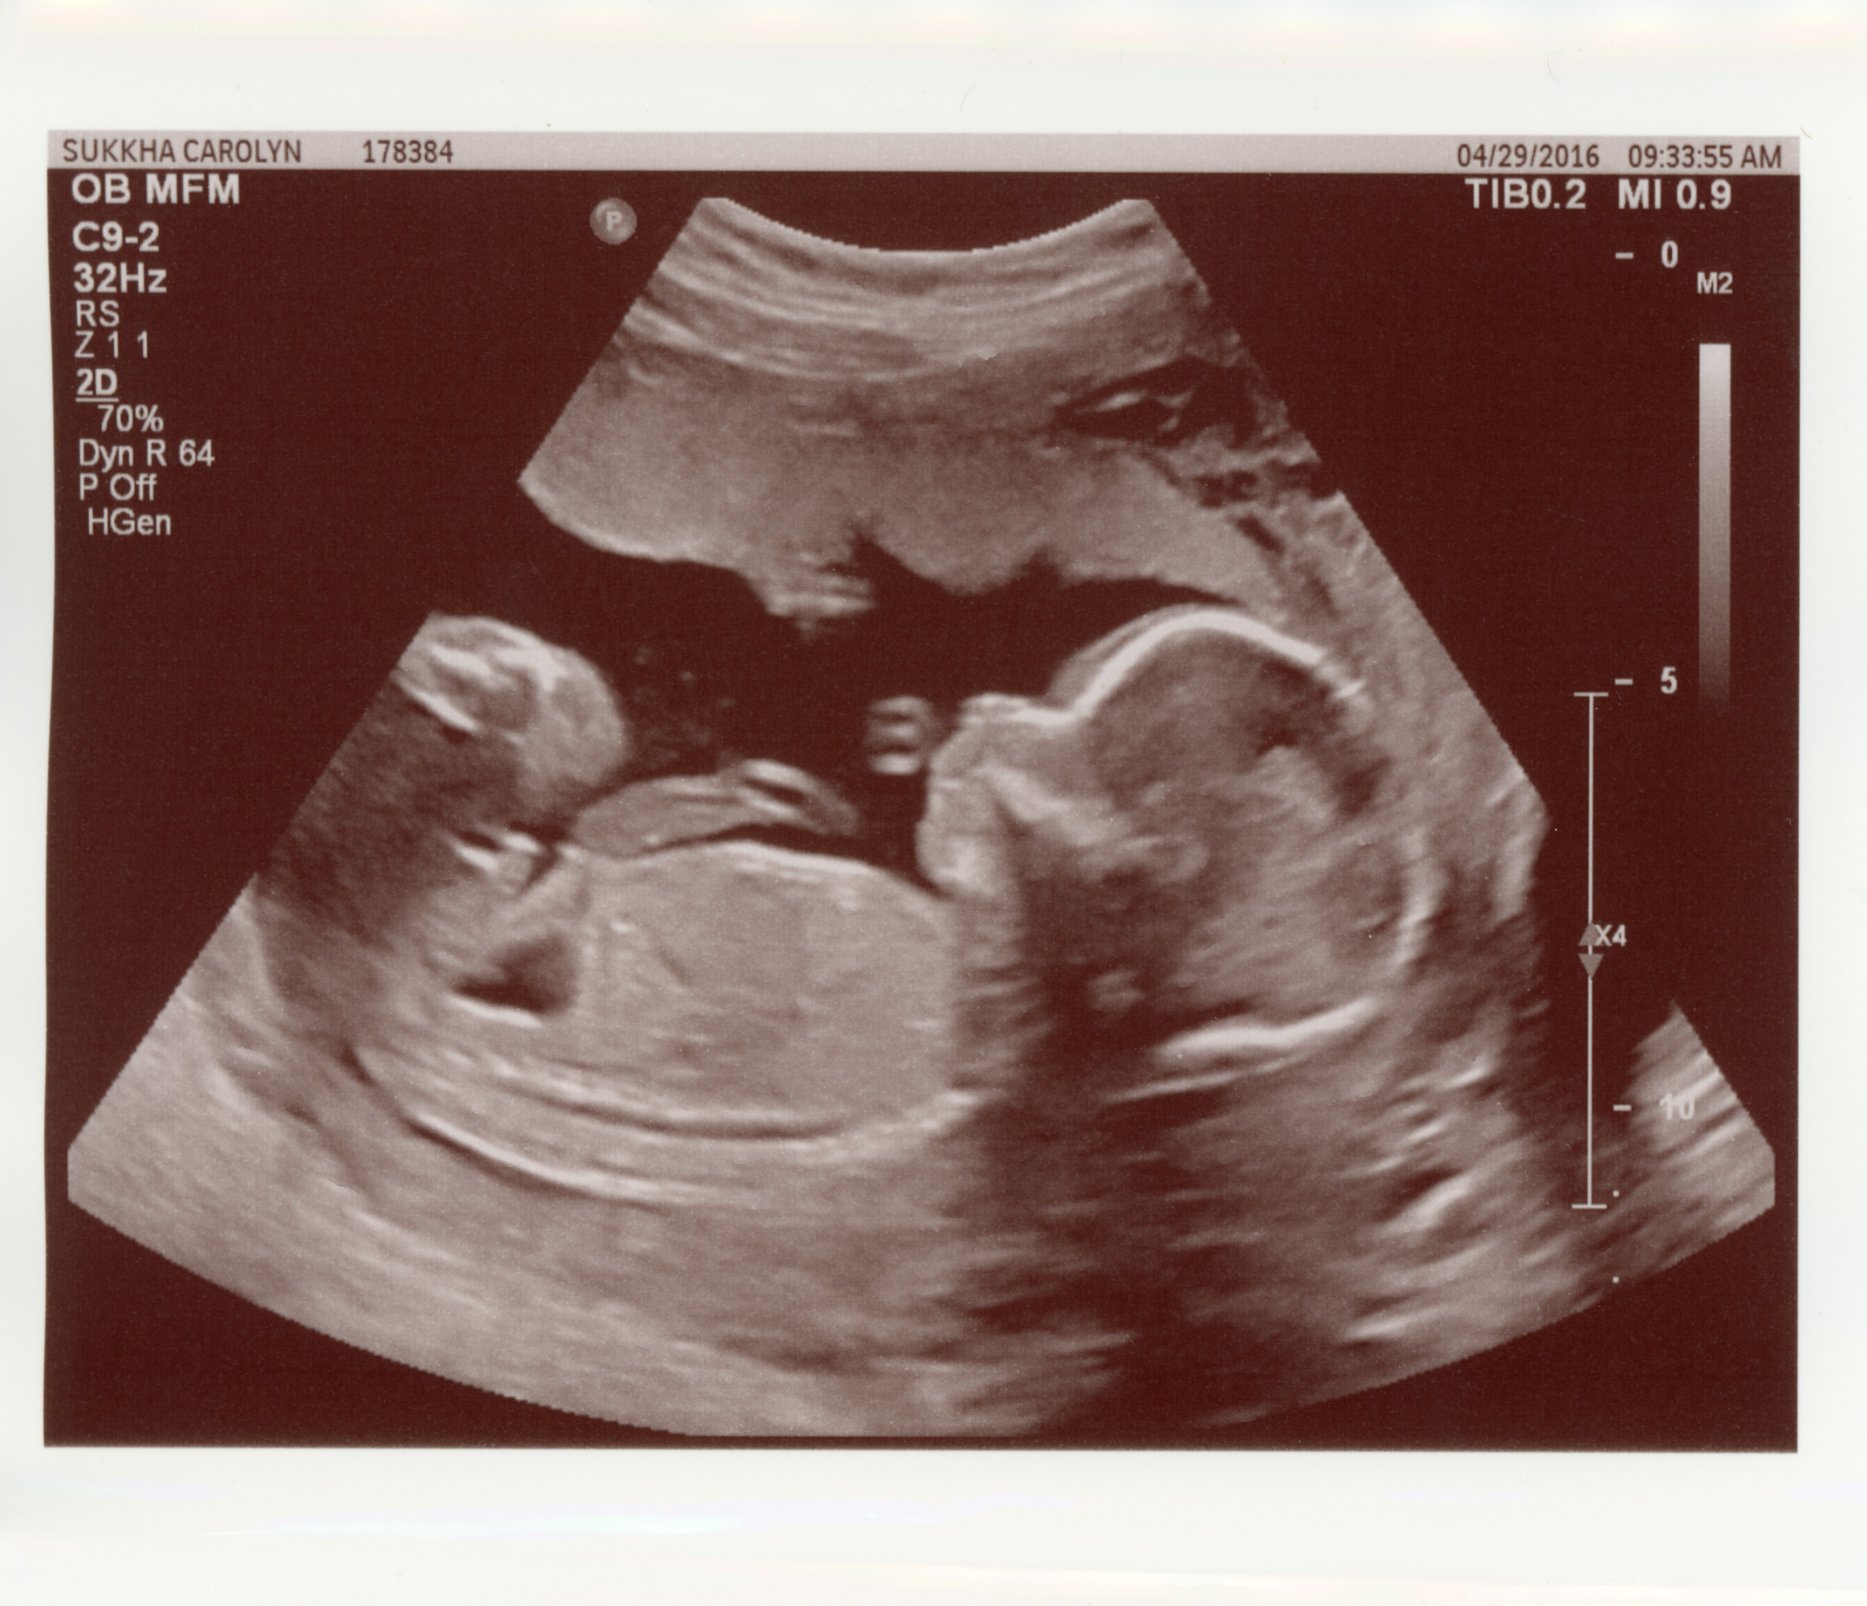

Had my anatomy scan today. She's measuring a little on the small side, 9 oz at 19w 5 d, which they said is in the 12th percentile, but otherwise she's doing great!